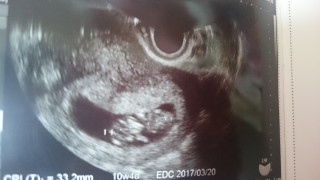

crl33.2ミリ。大きく育っていました。ここ数日で悪阻が酷くなりました。念願の30ミリを越えてとっても嬉しかったのですが、血液検査でトキソプラズマという病気にかかっていることが分かりました。 妊娠してから安易に野良猫に接したりした結果だと思います。妊娠が分かった方は是非気を付けて欲しいなと思いました。